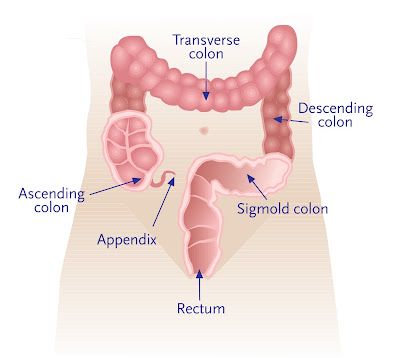

Ο καρκίνος του εντέρου, γνωστός και ως ορθοκολικός καρκίνος ή καρκίνος του παχέος εντέρου, εμφανίζεται στο παχύ έντερο (colon) ή στο ορθό (rectum). Ο καρκίνος του παχέος εντέρου (ΚΠΕ) αποτελεί παγκοσμίως τον τρίτο πιο συχνό καρκίνο στους άντρες και το δεύτερο στις γυναίκες, με πάνω από 1.2 εκατομμύρια νέες περιπτώσεις και 600000 θανάτους ετησίως.